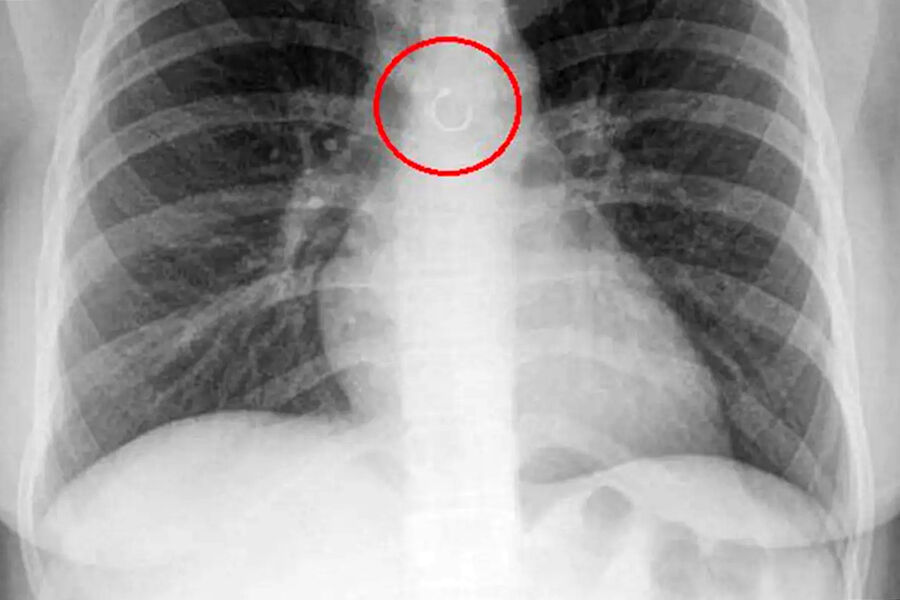

Женщина обнаружила, что потерянное кольцо в носу попало в ее легкие

В Мексике женщина обнаружила, что потерянное кольцо в носу попало в ее легкие, пишет Fox News.

Во время обследования выяснилось, что украшение из пирсинга в носу каким-то образом оказалось глубоко в дыхательных путях девушки и застряло в легких. Металлический элемент находился всего в полумиллиметре от аорты, что могло привести к опасным последствиям, добавили медики.